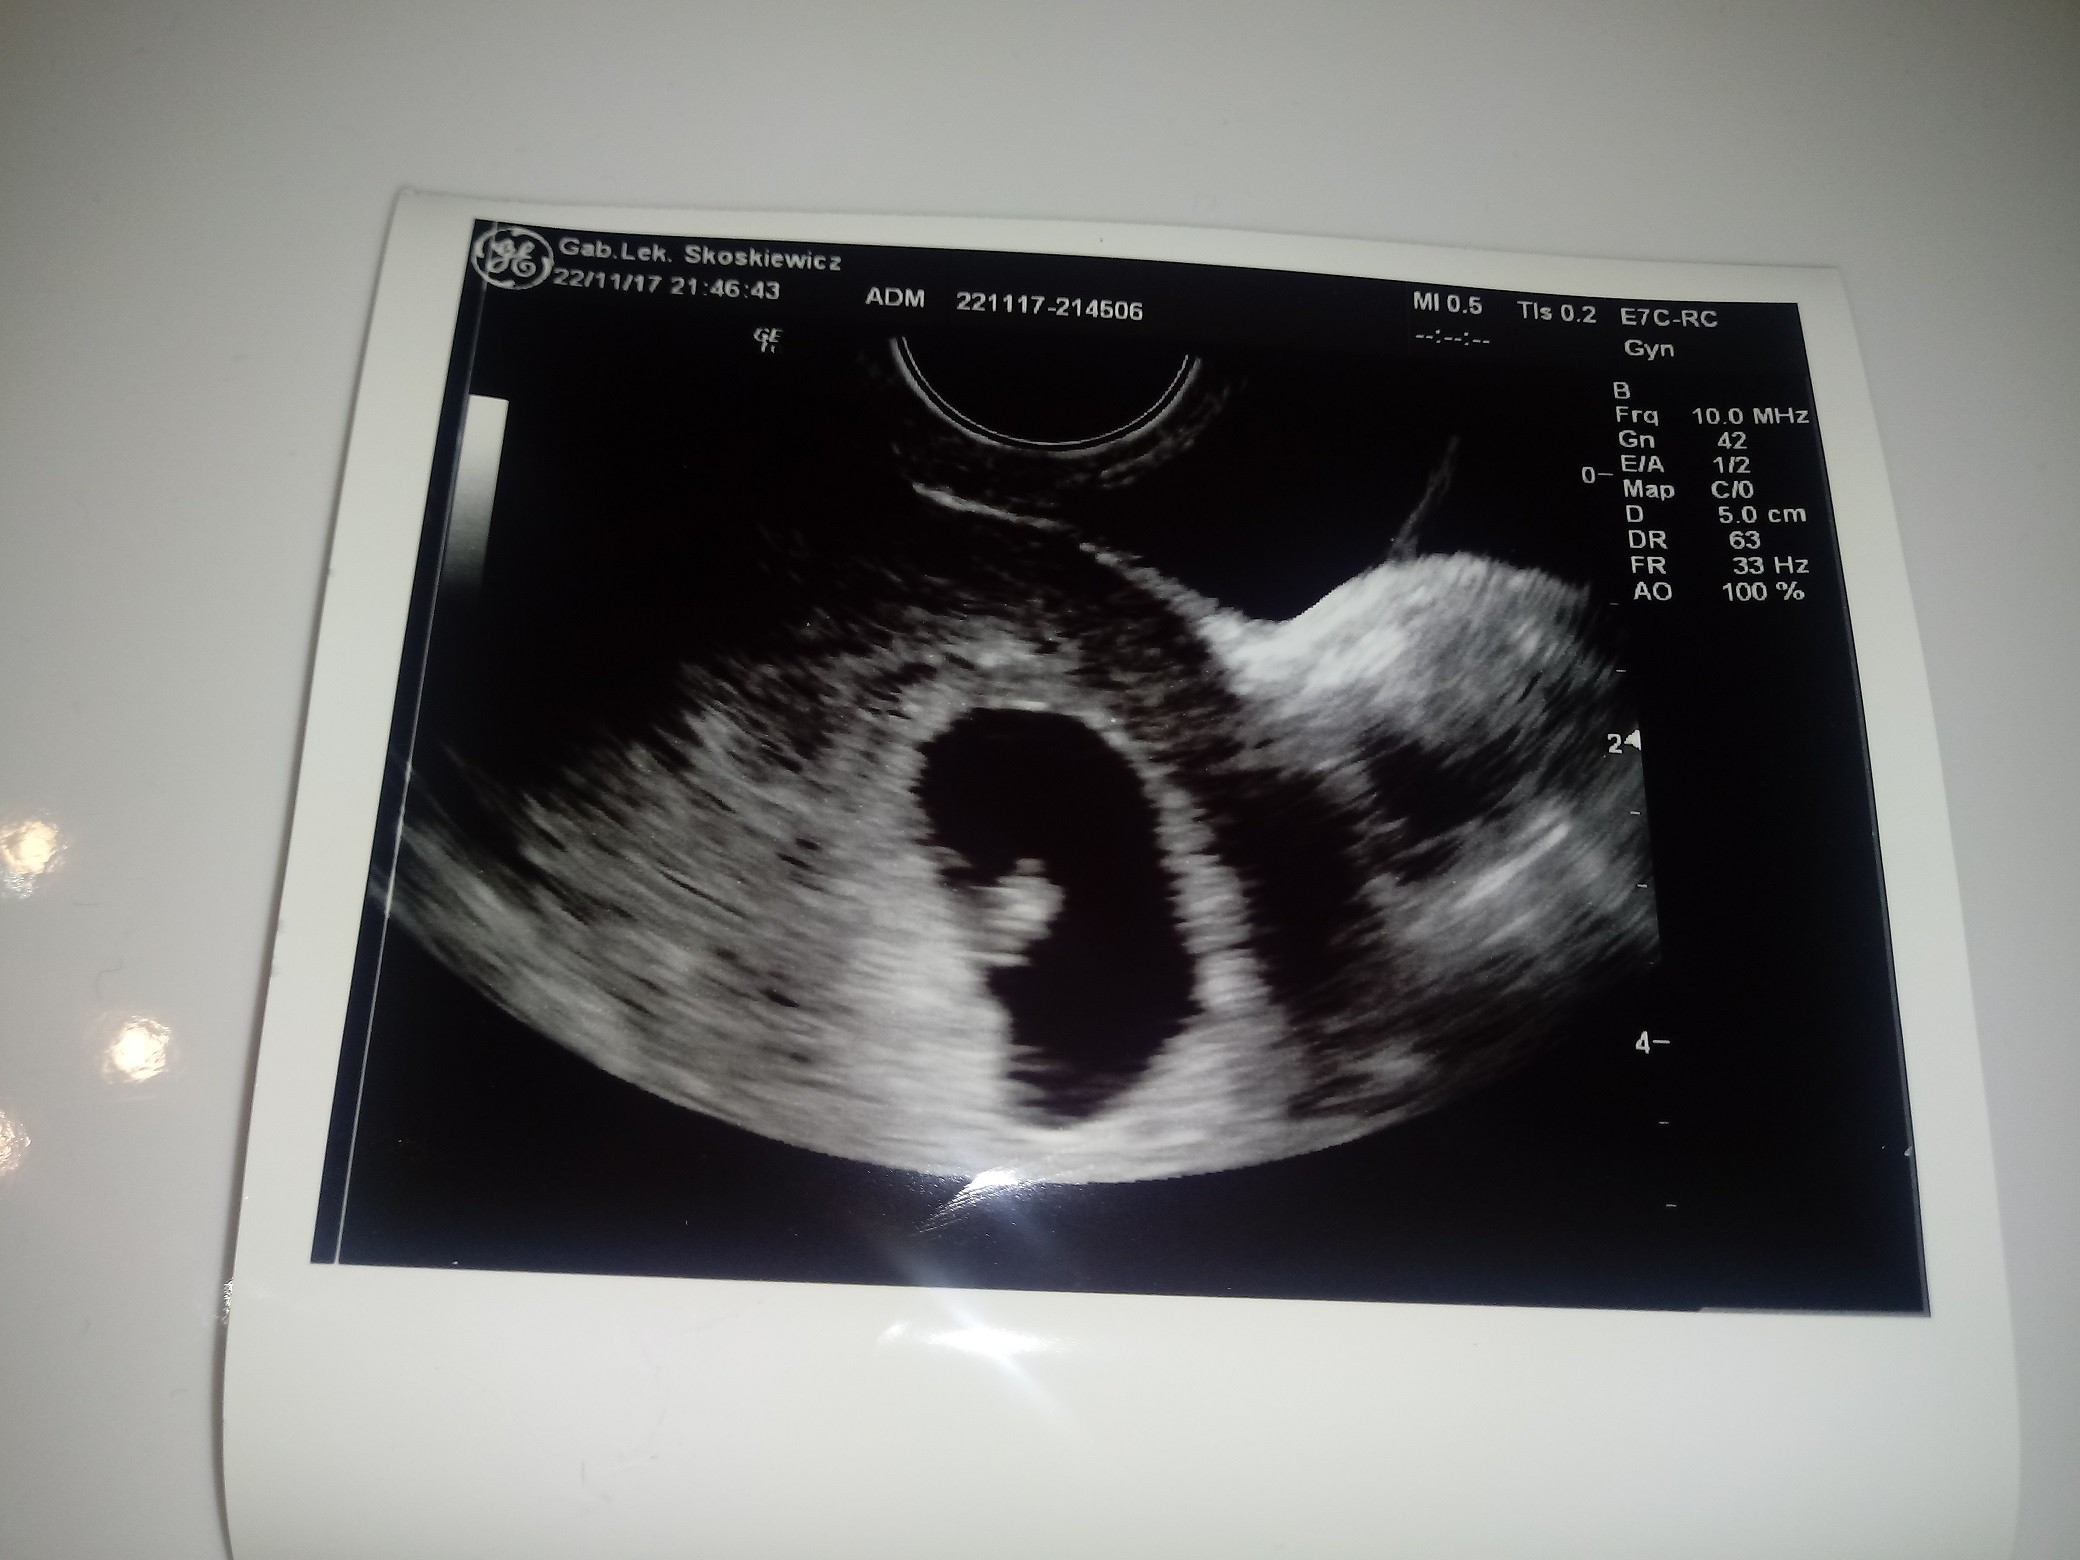

Jestem po wizycie. Dzidzia się ładnie rozwija i serduszko pięknie bije [emoji3][emoji8][emoji177]

A oto moja fasolinka

Zobacz załącznik 830056